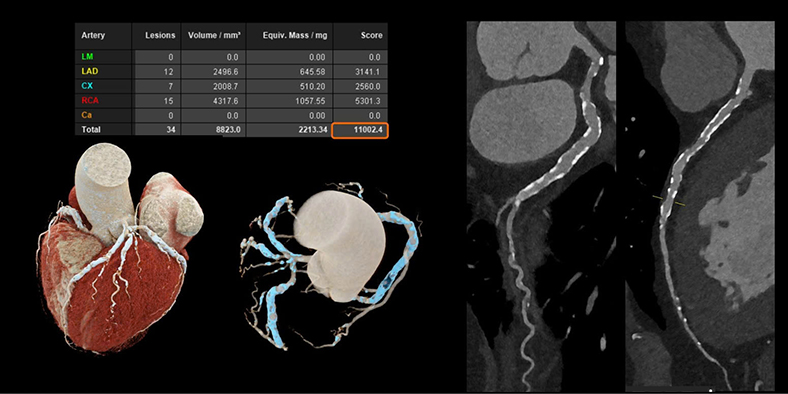

Với các bệnh tim mạch, đặc biệt ở những bệnh nhân đã đặt stent hoặc có mạch vành bị vôi hóa nặng - vốn là những trường hợp khó đánh giá bằng CT thông thường. Công nghệ này cho phép hình ảnh rõ ràng hơn đáng kể. Nhờ đó, bác sĩ có thể quan sát chính xác lòng mạch và các mảng xơ vữa, ngay cả khi bệnh nhân có nhịp tim cao hoặc loạn nhịp mà không cần sử dụng thêm thuốc hỗ trợ.

Hình ảnh mạch vành cho thấy độ rõ cao hơn, giảm nhiễu và giúp đánh giá chính xác hơn - Ảnh: Siemens Healthineers